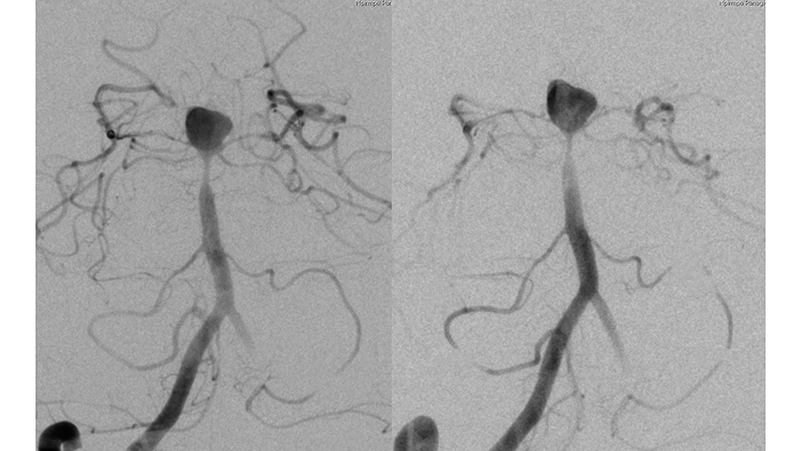

Εικόνα 3: Αγγειογραφία των έσω καρωτίδων αμφοτερόπλευρα, σε πλαγία προβολή: Βλέπουμε την οπισθίων αναστομωτικών ανφοτερόπλευρα. Δεν υπάρχει εφεδρεία από την πρόσθια κυκλοφορία προς το σύστημα των οπισθίων εγκεφαλικών αρτηριών αμφοτερόπλευρα.